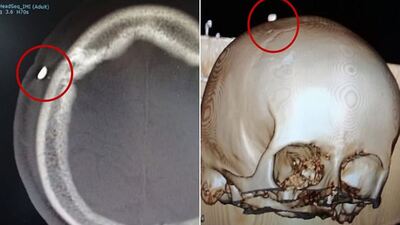

İngiliz gazete Daily Mail'de yer alan habere göre; hastanede kafasına dikiş atılan ismi verilmeyen çocuk, 5 gün sonra rahatsızlandı. Hastaneye kaldırılan çocuğa antibiyotik verildi ancak şikayetleri yine geçmeyince tarama yapıldı. Taramaların ardından çocuğun kafatasında diş tespit edildi.

TAM 12 GÜN SONRA ÇIKARTILDI

Isırılan çocuğun kafasındaki diş tam 12 gün sonra çıkartıldı. Amerikan Nörolojik Cerrahlar Birliği'ne göre; spor ve eğlence etkinlikleri, Amerikan çocuklar ve ergenler arasındaki tüm travmatik beyin yaralanmalarının yüzde 21'ine katkıda bulunuyor.